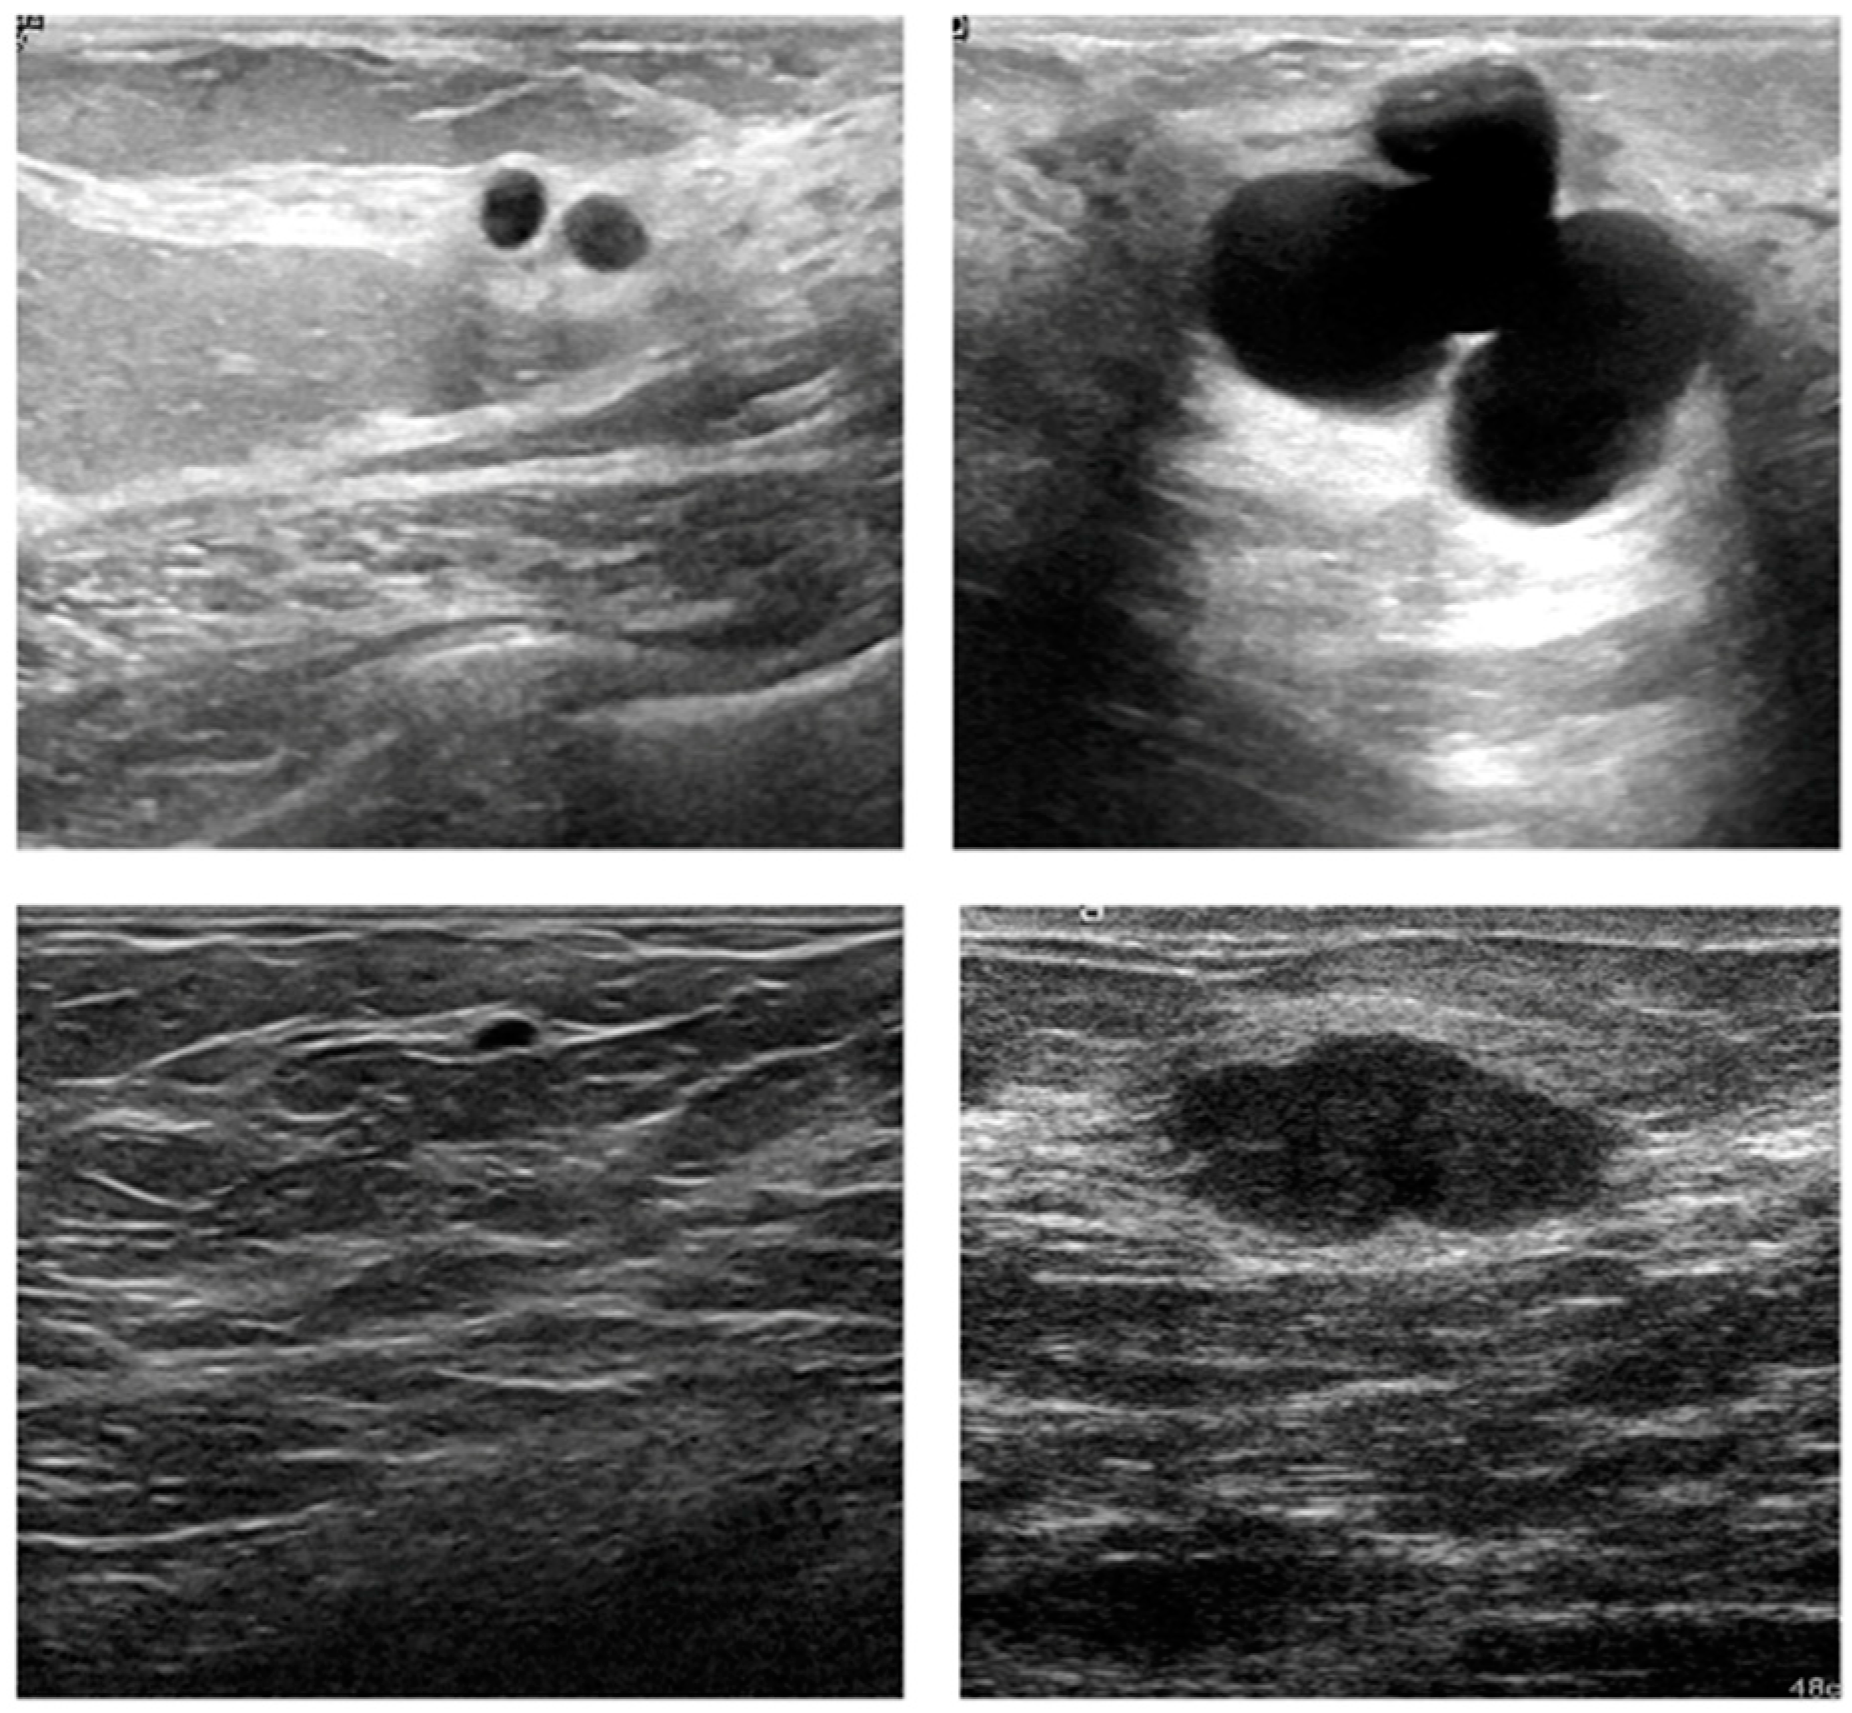

3.1. Visual Assessment

- Al-Dhabyani, W.; Fahmy, A.; Gomaa, M.; Khaled, H. Deep learning approaches for data augmentation and classification of breast masses using ultraound images. Int. J. Adv. Comput. Sci. Appl. 2019, 10, 618–627. [Google Scholar]

- Yap, M.H.; Pons, G.; Marti, J.; Ganau, S.; Sentis, M.; Zwiggelaar, R.; Davison, A.K.; Martí, R. Automated breast ultrasound lesions detection using convolutional neural networks. IEEE J. Biomed. Health Inform. 2018, 22, 1218–1226. [Google Scholar] [CrossRef] [PubMed] [Green Version]